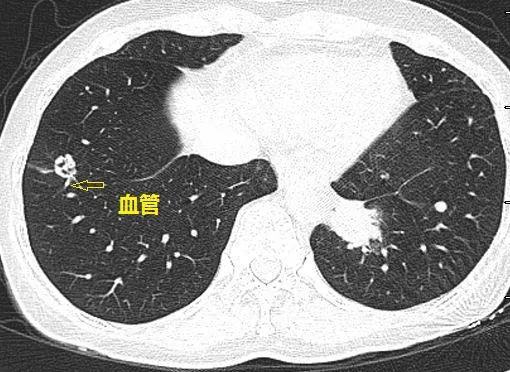

这个与血管相连的双肺多发小结节是怎样的神奇疾病